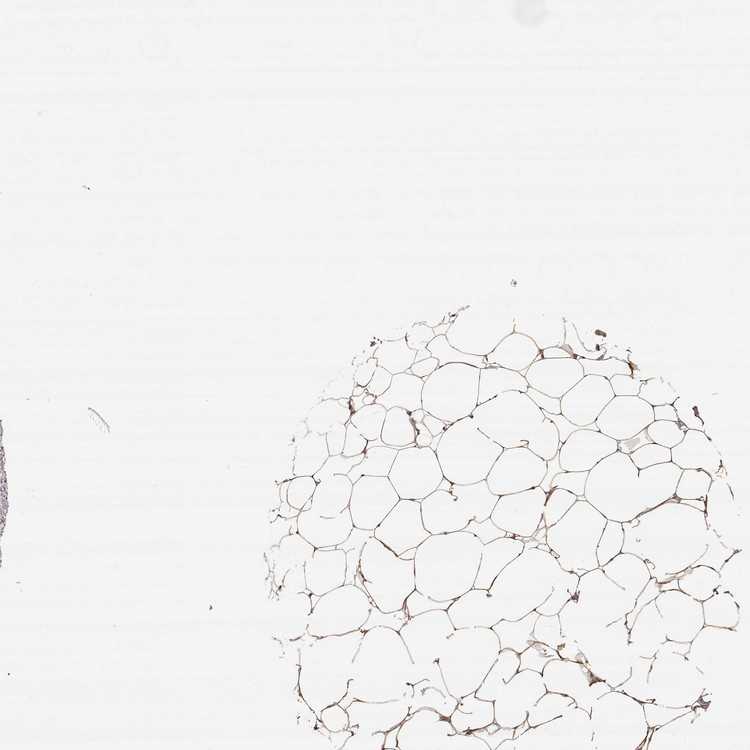

BREAST - Antibody stainingi

Antibody staining in the annotated cell types in the current human tissue is reported as not detected, low, medium, or high, based on conventional immunohistochemistry profiling in selected tissues. This score is based on the combination of the staining intensity and fraction of stained cells.

Each image is clickable and will lead to virtual microscopy that enables deeper exploration of all samples and also displays staining intensity scores, fraction scores and subcellular localization as well as patient and tissue information for each sample.

Antibody HPA000556

Adipocytes Medium

Glandular cells Medium

Myoepithelial cells Low